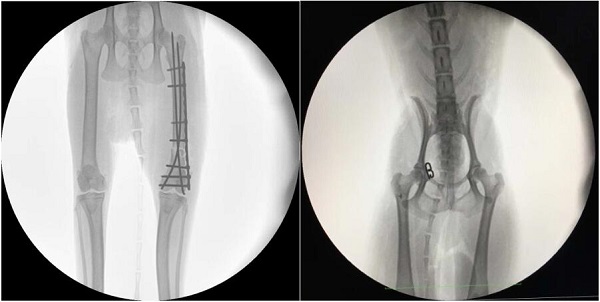

【寵物c臂機(jī)臨床圖像】